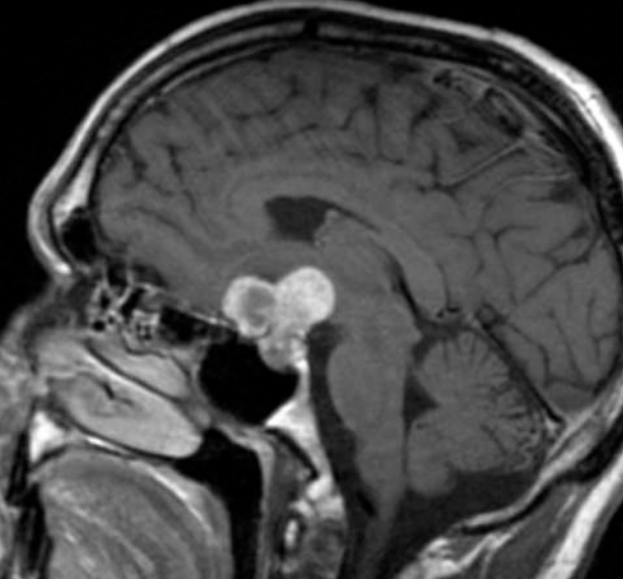

虽然颅咽管瘤被认为是一种良性肿瘤,但其发病率和死亡率相当高,经常侵袭邻近的结构,包括蝶鞍、下丘脑、视神经和三脑室...

颅咽管瘤在大脑区域发展,周围有许多关键结构,包括视觉通路、垂体、下丘脑、颞叶、脑干和主要的脑血管。这种复杂的颅内环境对放射剂量的传递...

颅咽管榴是多年来引起神经外科医师较大关注的一种良性肿瘤,其完整切除和治愈的可能性取决于我们对肿瘤与下丘脑、垂体柄和视器之间的复杂关系的认识...

颅咽管瘤是什么?不同解剖部位的颅咽管瘤可以是囊性、实性或囊性,有些肿瘤可能有一些钙化。 颅咽管瘤发生的主要部位是鞍区,也可以在鞍区、鞍区、...